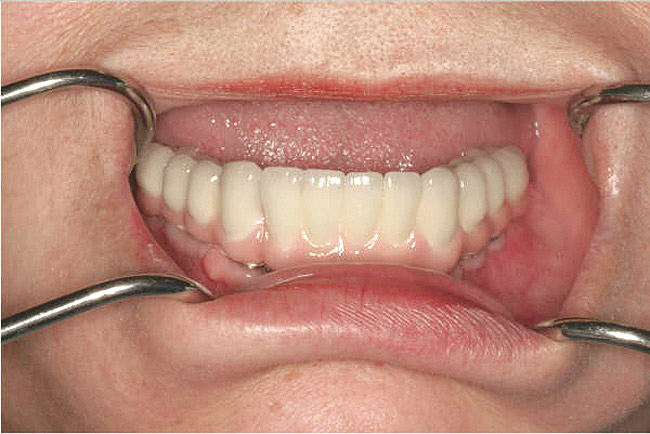

Figure 1  The crown height is measured from the alveolar crest to the occlusal table.

Figure 1

Figure 2  Vertical components of crown height space for a cement-retained restoration.

Figure 2

Figure 3   A crown height space < 15 mm necessitates a PFM material selection.

Figure 3

Figure 4  A crown height space > 15 mm necessitates a hybrid restoration.

Figure 4

Figure 5  The increased amount of metal required for this prosthesis greatly increases the laboratory costs.

Figure 5

Figure 6  The increased amount of metal required for this prosthesis greatly increases the laboratory costs.

Figure 6

Figure 7   A hybrid restoration requires less metal to fabricate.

Figure 7

Figure 8   A hybrid restoration requires less metal to fabricate.

Figure 8

Figure 9  Vertical components of crown height space for a bar-retained implant overdenture.

Figure 9

Figure 10a  Supra-eruption of the opposing arch, thus diminishing crown height space.

Figure 10a

Figure 10b  Supra-eruption of the opposing arch, thus diminishing crown height space.

Figure 10b

Figure 10c  Traditional fixed prosthodontics performed to level the opposing arch and regain sufficient crown height space.

Figure 10c

Figure 10d  Traditional fixed prosthodontics performed to level the opposing arch and regain sufficient crown height space.

Figure 10d

Figure 11a  Insufficient crown height space for bar overdenture because of the vertical dimension of the mandible.

Figure 11a

Figure 11b  Osteoplasty performed at the time of implant placement to gain sufficient crown height space.

Figure 11b

Figure 12  Horizontal spacing needed between the natural tooth and the implants and between the adjacent implants.

Figure 12

Figure 13  Radiograph depicting the necessity of horizontal placement parameters to prevent vertical defects from becoming horizontal defects.

Figure 13

Figure 14  Diagram of potential anterior-posterior spread based on implant placement and arch form.

Figure 14